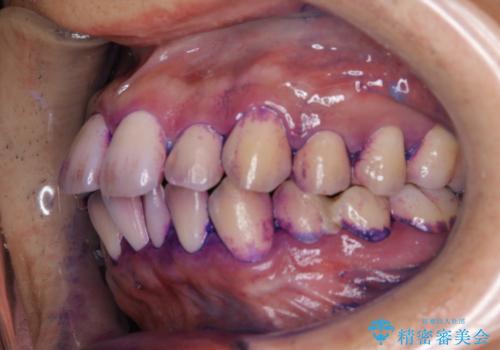

染め出しについて

口腔内にはたくさんの細菌がいるため、ヌルヌルとしたプラーク(歯垢)が自然に歯の表面に付きます。

このプラーク(歯垢)にはたくさんの細菌が潜んでおり、虫歯や歯周病・口臭などの最大の原因です。そのため、毎日の歯磨きでプラーク(歯垢)をキレイに取り除くことが、健康な歯を保つためには欠かせません。

しかし、プラークは歯の色と似ているため、見ただけでは付着しているかどうかがハッキリとは分かりません。

染め出し液を使ってプラークを染め出すことにより、普段の歯みがきで磨き残している場所を目で確かめることができます。

日々の歯磨きを上達するには、まずどこが磨けていないか認識することが大切です。